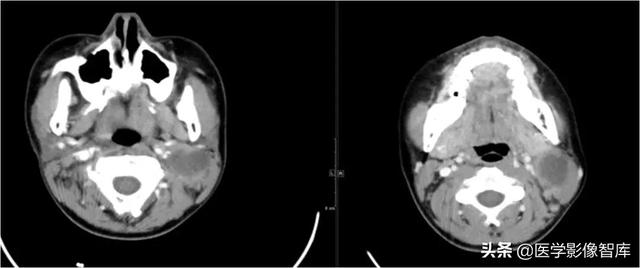

颌下间隙、颏下间隙

女,68岁,10天前自觉右侧下颌后牙区间断性钝痛,6天前发现右侧颌下区及颏下区肿胀,伴明显触压痛。

龋齿并冠周炎,咽旁间隙有肿大淋巴结。